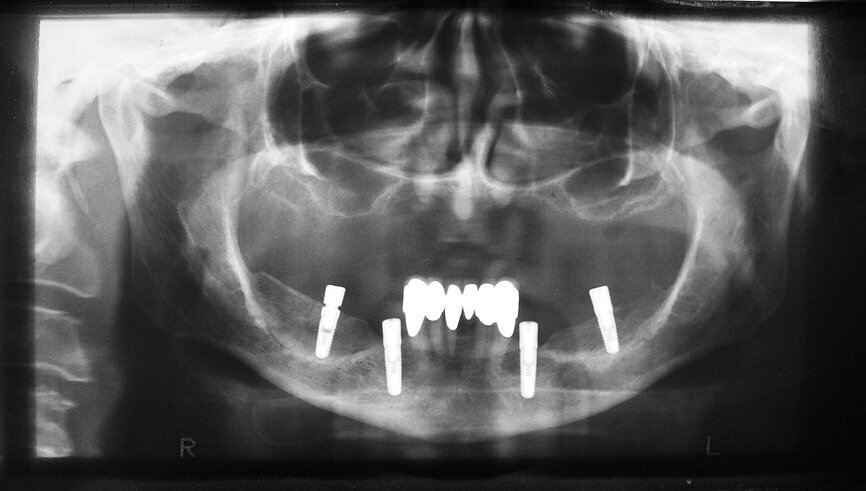

Fig. 11 : Tomographie panoramique dentaire du patient après la chirurgie aux fins du contrôle de la position des implants.

Deux petits lambeaux de pleine épaisseur ont également été décollés afin d’éliminer la vis d’ostéosynthèse utilisée pour stabiliser la greffe osseuse autologue de la chirurgie d’augmentation précédente (Fig. 9). L’insertion des implants a été réalisée à l’aide d’une clé à cliquet DRM et d’une douille standard, avec un couple de serrage prédéfini de 35–45 Ncm, afin de parvenir à une stabilité primaire maximale. Les façonneurs gingivaux ont été insérés avec un couple de serrage de 20 Ncm (Fig. 10) et, après l’insertion des implants, les lambeaux ont été suturés au moyen de fils non résorbables (Prolene 5/0). Les sutures ont été retirées après sept jours. Une tomographie panoramique dentaire postopératoire a permis de visualiser les implants insérés dans la mandibule. Les zones d’augmentation osseuse étaient également clairement reconnaissables sur les deux cotés (Fig. 11).